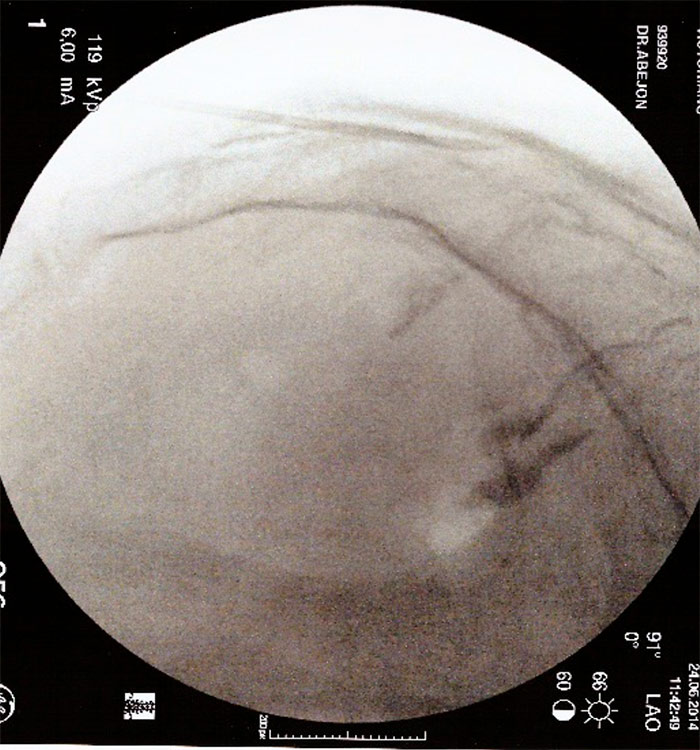

Con el paciente en decúbito prono, se coloca una almohada a la altura de la pelvis para corregir la lordosis fisiológica, y el arco de fluoroscopia en posición AP , con el  marcador radiopaco se localiza la línea media, se gira el arco de fluoroscopia a posición lateral para localizar el hiato sacro. Una vez localizado se infiltra con anestesia local de la piel, tejido celular subcutáneo, ligamento sacrocoxigeo y periostio, y se realiza punción con una aguja introductora con visión continúa hasta atravesar el ligamento sacrocoxigeo, se  administra contraste radiopaco (2-5ml) en visión continua y se comprueba su distribución. Posteriormente se vuelve a comprobar la distribución del contraste con el arco de fluoroscopia en posición anteroposterior (epidurografía). La epidurografía nos permitirá identificar las raíces que no se rellenan con contraste (fibrosis).

A continuación se introduce un catéter y se dirige hacia la zona de amputación radiológica, en el espacio epidural anterior. Con el arco de rayos en posición lateral, se inyectan 10ml de suero salino 0.9% con 1500v de hialuronidasa en la zona de amputación, posteriormente se inyecta de 3-5ml de contraste radiológico para visualizar la apertura del espacio, y a continuación se inyecta 9ml de Bupivacaina 0.25% y 40mg de triamcinolona. Se retira la aguja introductora y el catéter y se coloca un apósito. Hay autores que dejan el catéter durante 3 días y vuelven a inyectar el anestésico local y suero salino fisiológico al 10% (está en discusión). Con el catéter de RCE Cosman, se dirige a la zona amputada de contraste, se sigue el procedimiento anterior y además se intenta dirigir la punta del catéter debajo del pedículo que es donde se encontraría el ganglio de la raíz dorsal y se procede a hacer radiofrecuencia pulsada (estimulo sensitivo alrededor de 0.5v y el 45v, por un periodo de 2 a 8 minutos.